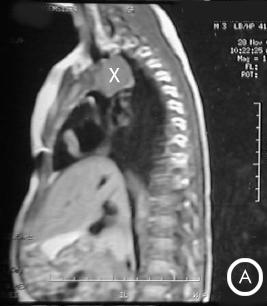

Resonancia Magnética

Corte longitudinal antero-posterior:

• Foto A: Corte longitudinal antero-posterior a la izquierda de la traquea. (X) = Masa mediastinal antero-superior en su extensión lateral izquierda de la traquea.